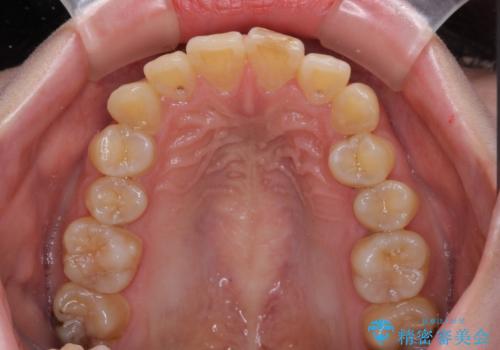

- ぶつけて欠けてしまった前歯を樹脂でつめていたものの、すり減りや変色が顕著とのことで来院された患者様です。

詰め物の詰め直しとオールセラミッククラウンの双方をご提案し、患者様ご希望によりオールセラミッククラウンにて補綴治療を行うこととしました。

歯列全体に表面の着色があったため、クリーニングとホワイトニングを事前に行い、ホワイトニング後1ヶ月ほどおいて、色の落ち着いたところで色合わせを行いました。

本物の歯のような仕上がりとなりました。